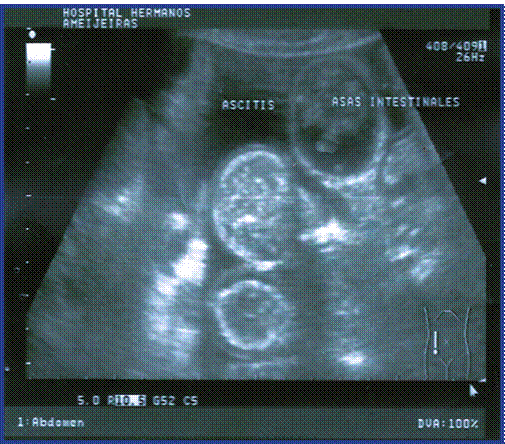

Los estudios imagenológicos reportaron radiografía de tórax sin alteraciones, ultrasonido abdominal que informa líquido libre en cavidad (fig.1), pero llamó la atención la existencia de asas intestinales delgadas (duodeno y yeyuno), ligeramente distendidas con líquido en su interior y pobre peristalsis observándose íleon terminal rígido, de aspecto inflamatorio a descartar ileítis regional (Figura. 2), duodeno engrosado con aspecto inflamatorio del patrón mucoso con sospecha de úlcera en segunda porción, el resto sin alteraciones. (Figura 1 y 2).